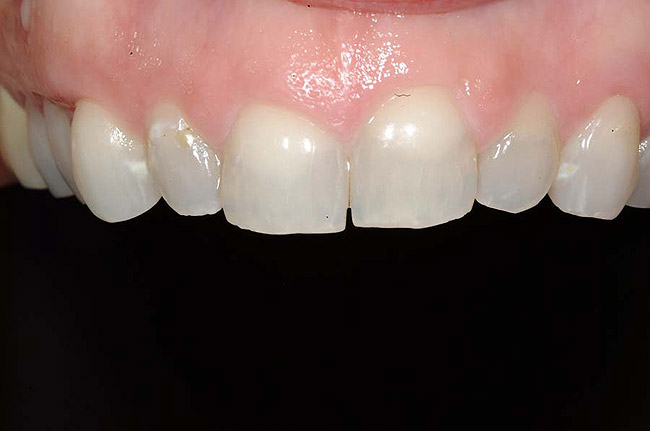

Figure 1 and Figure 2 Preoperative views of a female patient in her mid-50s who presented with a chief complaint of dissatisfaction with the appearance of her smile. Examination revealed multiple fractures, hypocalcification, shortened clinical teeth due to wear, and an asymmetrical smile line. Teeth Nos. 6 through 11 were treatment planned for porcelain laminate veneers.

In fact, scientists evaluating the long-term functionality of porcelain laminate veneers after 1 to 10 years of service observed that they had been placed for such reasons as correcting fractured and worn anterior teeth, treating surface enamel defects, and changing the appearance of intrinsically discolored dentition (Figure 2');" rem="#ip:figure1 and Figure 2">Figure 1 and Figure 2).2 These researchers found that the porcelain laminate veneer concept provided excellent esthetic and conservative restorations. In other studies, researchers observed 5-year success rates with porcelain laminate veneers,3 commenting that they offer a reliable and effective procedure for the conservative and esthetic treatment of anterior dentition.